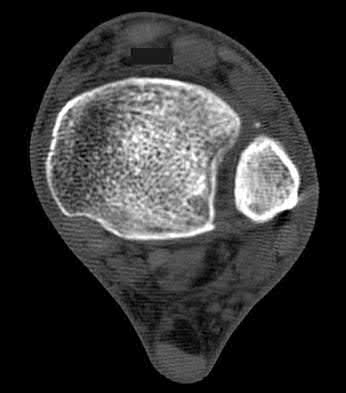

3. # Which of the following is not an appropriate implant for treatment of the fracture seen in Figure A?

1. Cephalomedullary nail

2. External fixation

3. Proximal femoral locking plate

4. 95 degree blade plate

5. Sliding hip screw Corrent answer: 5

The image shows a reverse obliquity intertrochanteric hip fracture.

According to the referenced article by Haidukewych et al, unstable peritrochanteric hip fractures have a worse outcome (failed in 9/16 cases) if treated with a sliding hip screw. Two additional factors that were found to have a strong correlation with postoperative failure (nonunion, loss of reduction) were poor reduction and poor implant placement. In this study, fixed angle devices were superior. Intramedullary fixation has the added advantage of a shorter lever arm and less potential for fracture collapse and limb shortening.

The IMN also acts as a medial buttress.

According to Sanders et al, the dynamic condylar screw (DCS) can also be used in subtrochanteric models, but should not be used if extensive comminution is seen, as they reported a high failure rate with DCS in these fractures if highly comminuted. They report a 77% overall union rate with this device.